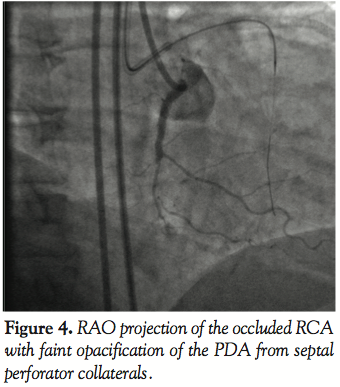

Case 2. A 50-year-old male with known occlusion of his RCA and inferior wall ischemia was referred for angiography. Bilateral femoral access with 8 Fr sheaths was obtained and simultaneous injections of the RCA and left coronary were performed (Figure 4) with a JR4 guiding catheter in the RCA. The CTO was successfully crossed using the antegrade approach and the GuideLiner catheter was then used to deliver long DES successfully (Figure 5). The final angiogram demonstrated the RCA successfully recanalized and a diffuse negatively modeled distal vessel (Figure 6).

Chronic total occlusions represent a unique challenge with respect to the diffuse nature of the disease even proximal to the occluded segment of the vessel and the small negatively remodeled distal target vessel. The GuideLiner catheter lends itself to use in this lesion subset because of the ability for deep engagement of the guiding catheter atraumatically and providing the support necessary for delivery of long drug-eluting stents for definitive treatment. The safety of the GuideLiner when used for deep intubation relies on the absence of a primary curve for the extension. It provides a safer alternative to using aggressive guiding catheters like the Amplatz left curves for the RCA. This is amply demonstrated in the second case in which the RCA chronic total occlusion was successfully treated with deep atraumatic engagement of the RCA ostium and subsequent delivery of long relatively inflexible first generation drug-eluting stents. The device allows for robust support for secure delivery of equipment to distal segments of the coronary tree. During in vitro testing, when extended 15 cm into the vessel, the 6 Fr GuideLiner catheter provides greater back up support than even an 8 Fr guiding catheter.

In the third, fourth, and fifth cases, the reason for the development of this device, facilitating distal stent delivery, is demonstrated. Commonly used methods to overcome difficulty with stent delivery include straightening of the vessel with a buddy wire, use of an anchor balloon, and using large diameter guiding catheters with more supportive curves. The GuideLiner facilitates delivery of stents to distal segments of the coronary vessel (Figures 4 and 5) by allowing safe deep vessel intubation. This provides the necessary extra back-up support needed for stent delivery. In an era when radial artery intervention is making a comeback into the mainstream, this may have added significance because the vast majority of cases via the radial artery are performed with 6 Fr guiding catheters. Also because of the angle of entry from the radial approach into the aortic sinus, coaxial guide placement is difficult. The GuideLiner catheter may allow for maintaining coaxial guide orientation. In case 3, a long circumflex artery stenosis was treated with deep engagement of the GuideLiner catheter to deliver 2 long DES as opposed to several shorter length drug-eluting stents. This may have incremental value in an era of cost containment by treating long lesions with fewer drug-eluting stents, thus lowering the cost per case.